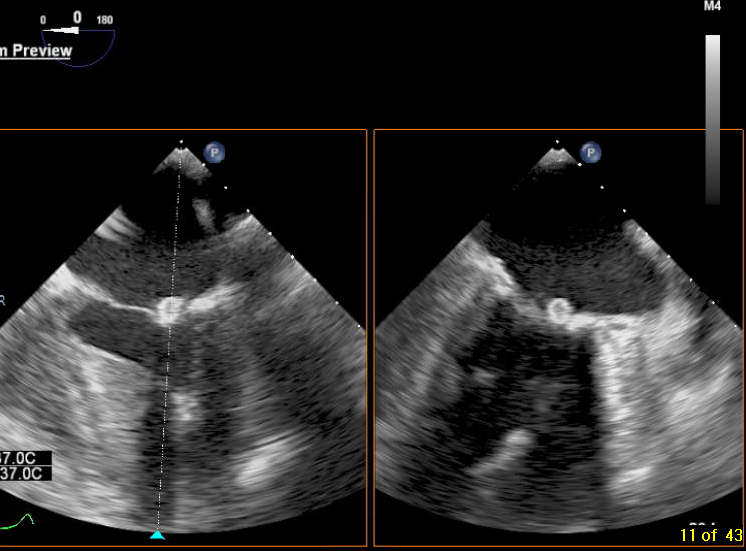

Post your answers! Challenge of the Week: TEE 50 F w a h/o ESRD presenting for TEE to evaluate an abnormal mitral finding. She has no reported infectious symptoms. What’s the diagnosis and what’s the typical management? drive.google.com/file/d/1SDW6g-… drive.google.com/file/d/1YTBOW6…

Post your answers! Challenge of the Week: TEE

50 F w a h/o ESRD presenting for TEE to evaluate an abnormal mitral finding.  She has no reported infectious symptoms.  What’s the diagnosis and what’s the typical management?